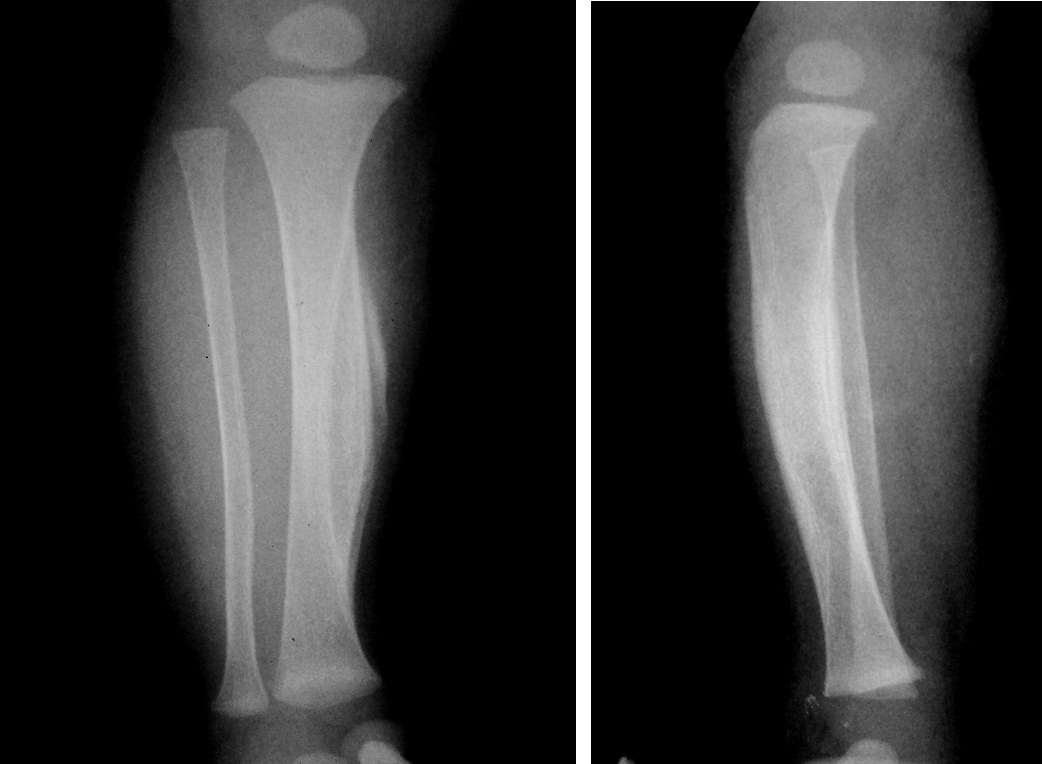

При врожденном заболевании Камурати-Энгельманна наблюдается ограничение подвижности в бедренных и плечевых суставах. В этих областях, а также в большеберцовых костях, возникают интенсивные болевые ощущения. Мышечная масса остается недостаточно развитой. В редких случаях может происходить поражение затылочной области и нарушения в формировании свода черепа у ребенка. Теменные кости срастаются быстрее, чем обычно. Часто наблюдается характерная «утинная» походка.

Эти изменения могут вызывать болевые ощущения и дискомфорт у ребенка. Также возможно уплотнение трубчатых костей, ключиц и искривление большеберцовых костей.

- рентгенография;

- компьютерная томография (КТ);